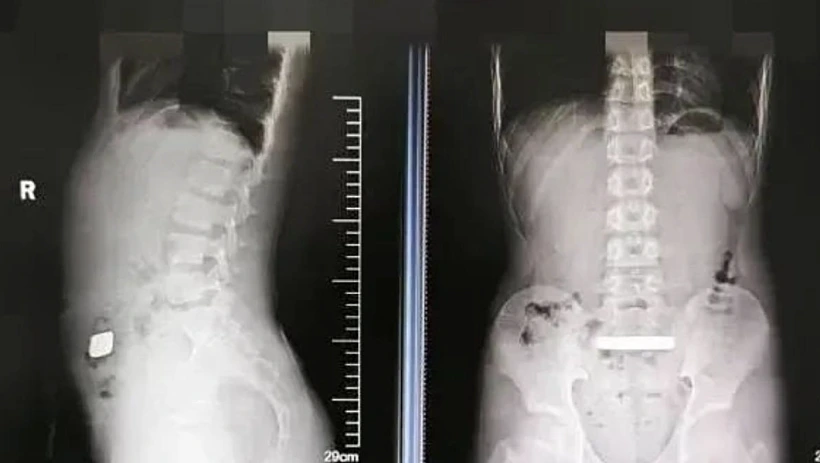

הוריו של הילד מיהרו לקחת אותו לחדר המיון בבית החולים לילדים של אוניברסיטת סוג'ואו, שם התגלה בצילום רנטגן שנערך לילד חפץ מתכתי כבד במרכז מערכת העיכול שלו.

בהמשך, התגלה כי מדובר במטיל זהב - שבשל גודלו של ומהחשש שהוא עלול לגרום לחסימה או לפגיעה פנימית, הוחלט לאשפז את הילד במחלקה לכירורגיה כללית.

בתחילה, הרופאים ניסו לגרום למטיל להיפלט באופן טבעי באמצעות חומרים משלשלים, אך לאחר יומיים של מעקב, ולאחר שצילומים נוספים הראו שהמטיל לא זז ממקומו, הוחלט לבצע ניתוח להוצאתו. בשל גילו הצעיר של הילד ותפקוד מערכת העיכול השברירית, בוצעה פעולה אנדוסקופית זעירה. הניתוח ארך כ-30 דקות, והסתיים בהצלחה. הילד חזר לאכול ולשתות כרגיל כבר ביום שלמחרת, ושוחרר לביתו ללא סיבוכים.